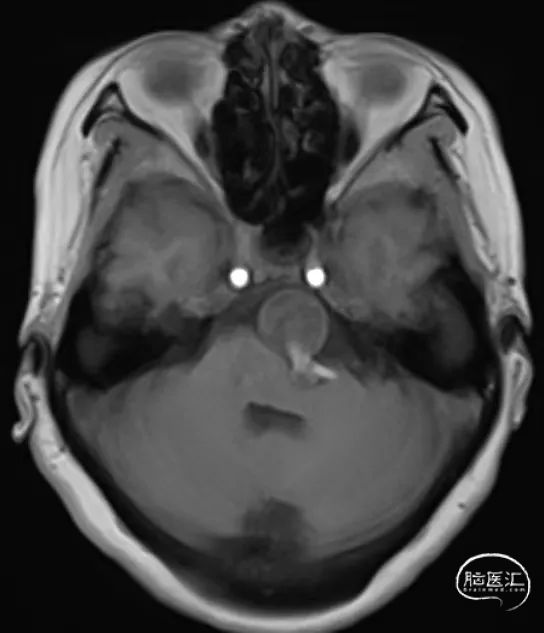

院前MRI

现病史:5年前,患者出现不明原因头痛,头晕,尚可耐受,未作进一步检查治疗。2024.4.23,头痛、头晕症状加重,无肢体无力,无意识丧失,无言语障碍。在当地医院行MRI检查提示:椎基底动脉多发动脉瘤。为进一步治疗,转入我科。